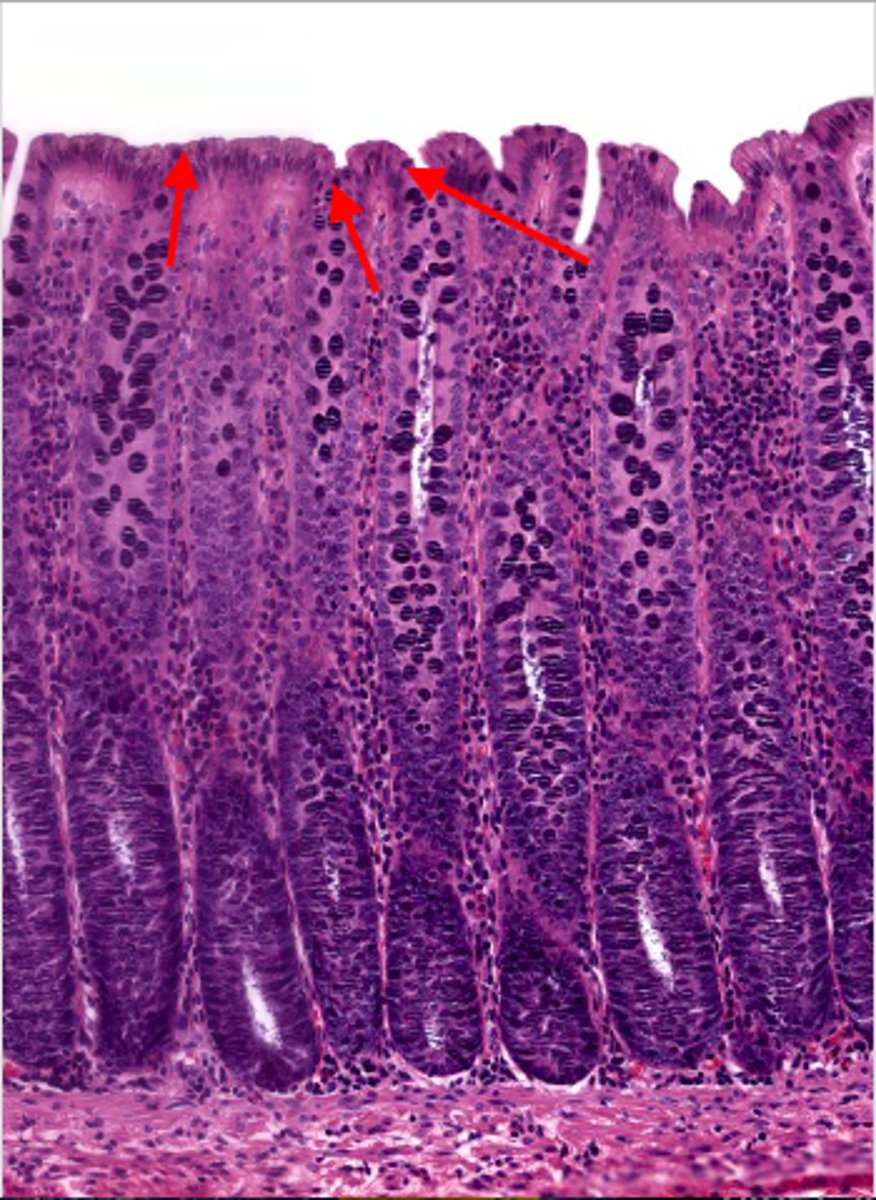

jejunum (histology)

simple columnar epithelium

what kind of epithelium lines the mucosa of the jejunum?

villi (jejunum)

intestinal crypts (jejunum)

lumen (jejunum)

mucosa (jejunum)

mucosal epithelium (jejunum)

lamina propria (jejunum)

muscularis mucosa (jejunum)

submucosa (jejunum)

contains glands and blood supply

muscularis externa (jejunum)

serosa/adventitia (jejunum)